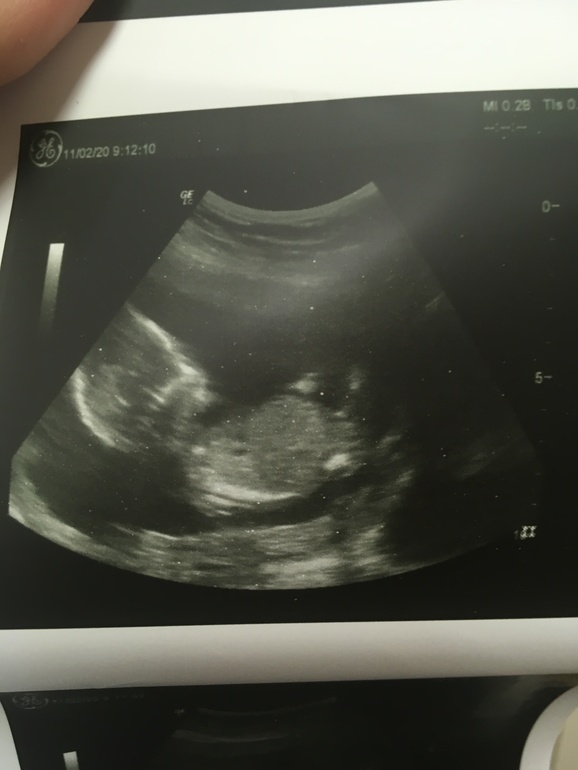

Вызывают, спокойно захожу, ложусь, оголяю живот и замираю в ожидании. Передо мной большой телевизор, видно хорошо. Врач начинает водить по животу и я вижу малыша. Но блин, мне кажется, или он не двигается!!! Внутри паника и голос - "Сердце!!! Включите сердце!!!"

Успокаиваюсь, когда замечаю, что моя крошка двигает ручками и ножками)))) И как же она подросла

Врач начинает все показывать, рассказывать, а я завороженно смотрю на свое Счастье) Ручки у лица, ножки поджал - не хочет показываться)))

Малыш вытягивает ножки и я открывается нам - СЫНОЧЕК

Сердечко билось ровно - 150 ударов, зато мое готовы было выпрыгнуть из груди.

Все соответствовало сроку - начале 16 недели, все органы в норме, воды и плацента 15( мм) тоже.

Я получила заветные фото своего "инопланетянина" и счастливая поехала домой)